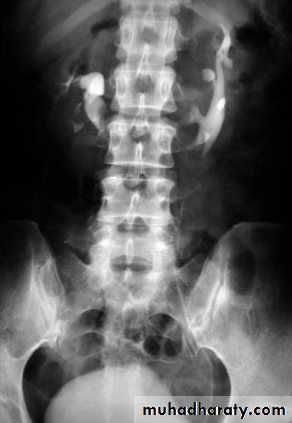

KUB

The IVU series consist of:1-KUB film…To identify any calcification like stones or nephrocalcinosis.

CALCULIMost renal stones are calcified and show varying density on plain x-ray films.

Pure uric acid & xanthine stones are radiolucent on plain radiography, but are well seen at CT or US.

Plain film is more sensitive than US for detecting ureteric calculi.